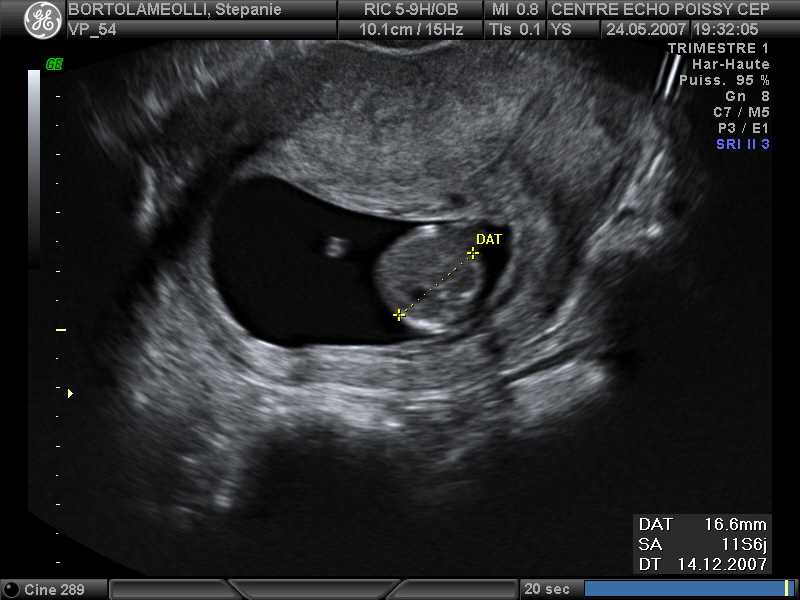

Echographies

Mai 2007